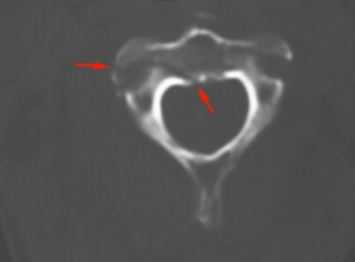

КТ. Перелом тела С2 (красные стрелки).